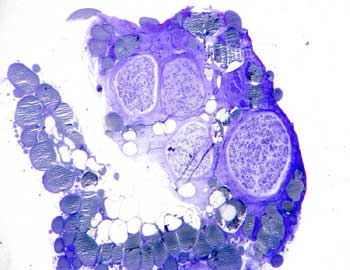

Visión general: el análisis histológico muestra vasos de mediano y pequeño calibre. Un vaso central de pared gruesa de características arteriales, en la que se distingue perfectamente las tres túnicas o capas vasculares.

Visión específica: túnica íntima constituida por un endotelio en contacto con la luz y un tejido subintimal con fibras colágenas y fibroblastos, separada mediante la capa limitante elástica interna de la túnica media, con células musculares lisas dispuestas concéntricamente a la luz, y la túnica adventicia externa rica en fibras colágenas y vasa vasorum que queda separada de la túnica anterior por la delgada lámina elástica externa. Las estructuras vasculares acompañantes de menor tamaño corresponden a venas, cuyas luces son irregulares, revestidas por la capa íntima limitada a endotelio, la capa media menos prominente y con células musculares con una disposición más helicoidal y la capa adventicia que es la túnica externa con tejido conjuntivo laxo. En ella observamos además varios nervios en corte longitudinal y transversal.